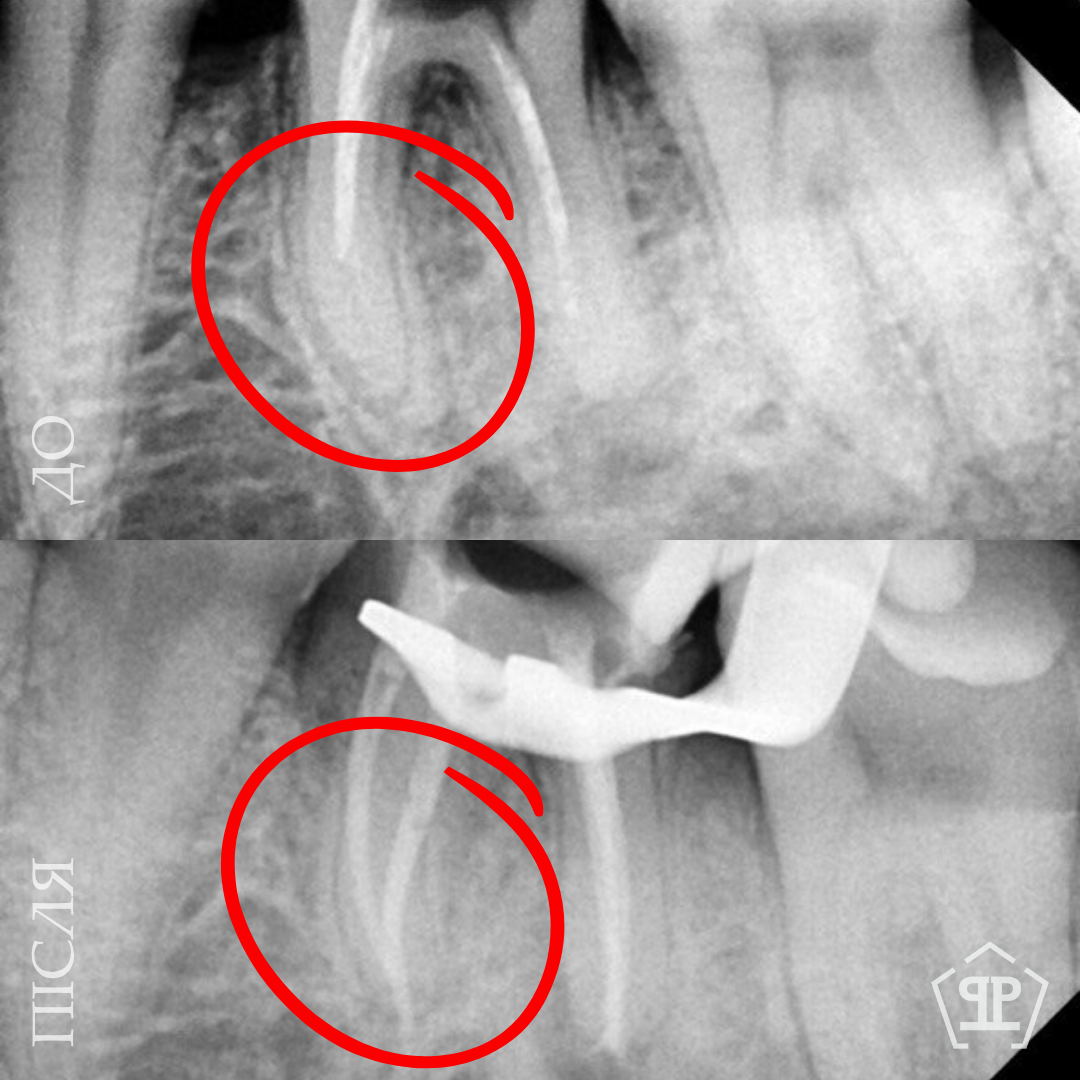

Перелечивание корневых каналов. Пациент обратился с признаками воспалительного процесса в верхнем зубе. Выявлены незапломбированные корневые каналы. Выполнен тщательное перелечивание с последующим герметическим пломбированием.

Пациент нуждался в повторном лечении корневых каналов из-за осложнений предварительного лечения. Выполнено извлечение анкерного штифта, перелечивание корневых каналов, очищение и пломбирование с учетом анатомических особенностей зуба.

Во время диагностики обнаружен отлом фрагмента инструмента в корневом канале. Выполнено его безопасное извлечение, повторное перелечивание каналов, очистку и герметичное пломбирование.

Перелечивание с удалением двух переломанных инструментов. Пациент обратился с осложнением предварительного эндодонтического лечения. В каналах были обнаружены два переломанных инструмента. Выполнены их удаление и пломбирование каналов с соблюдением современных эндодонтических протоколов.

Перелечивание корневых каналов. Пациент обратился с симптомами, свидетельствующими о недостаточном предварительном лечении. Выполнены перечисления корневых каналов, тщательная очистка и повторная пломбировка для достижения полной герметичности и предотвращения рецидива воспаления.

Первичное лечение корневых каналов. Лечение пульпита, возникшего вследствие глубокого кариеса.